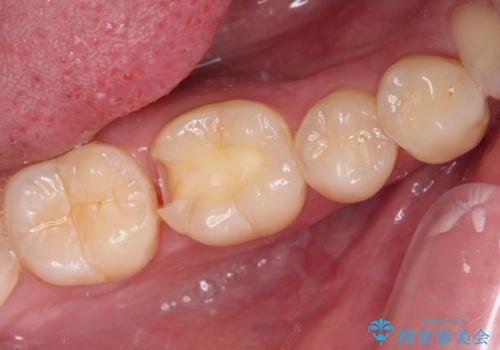

- 右下の奥歯が噛んだ時に痛み、冷たいものがしみることを主訴として来院された患者様です。

精査の結果、歯が欠けていてその下に虫歯が認められました。

また、咬合面(歯の噛む面)に以前治療した樹脂の詰め物があるため、一度外して虫歯を完全に除去し、

精度の高いセラミックインレーにて修復処置することとしました。